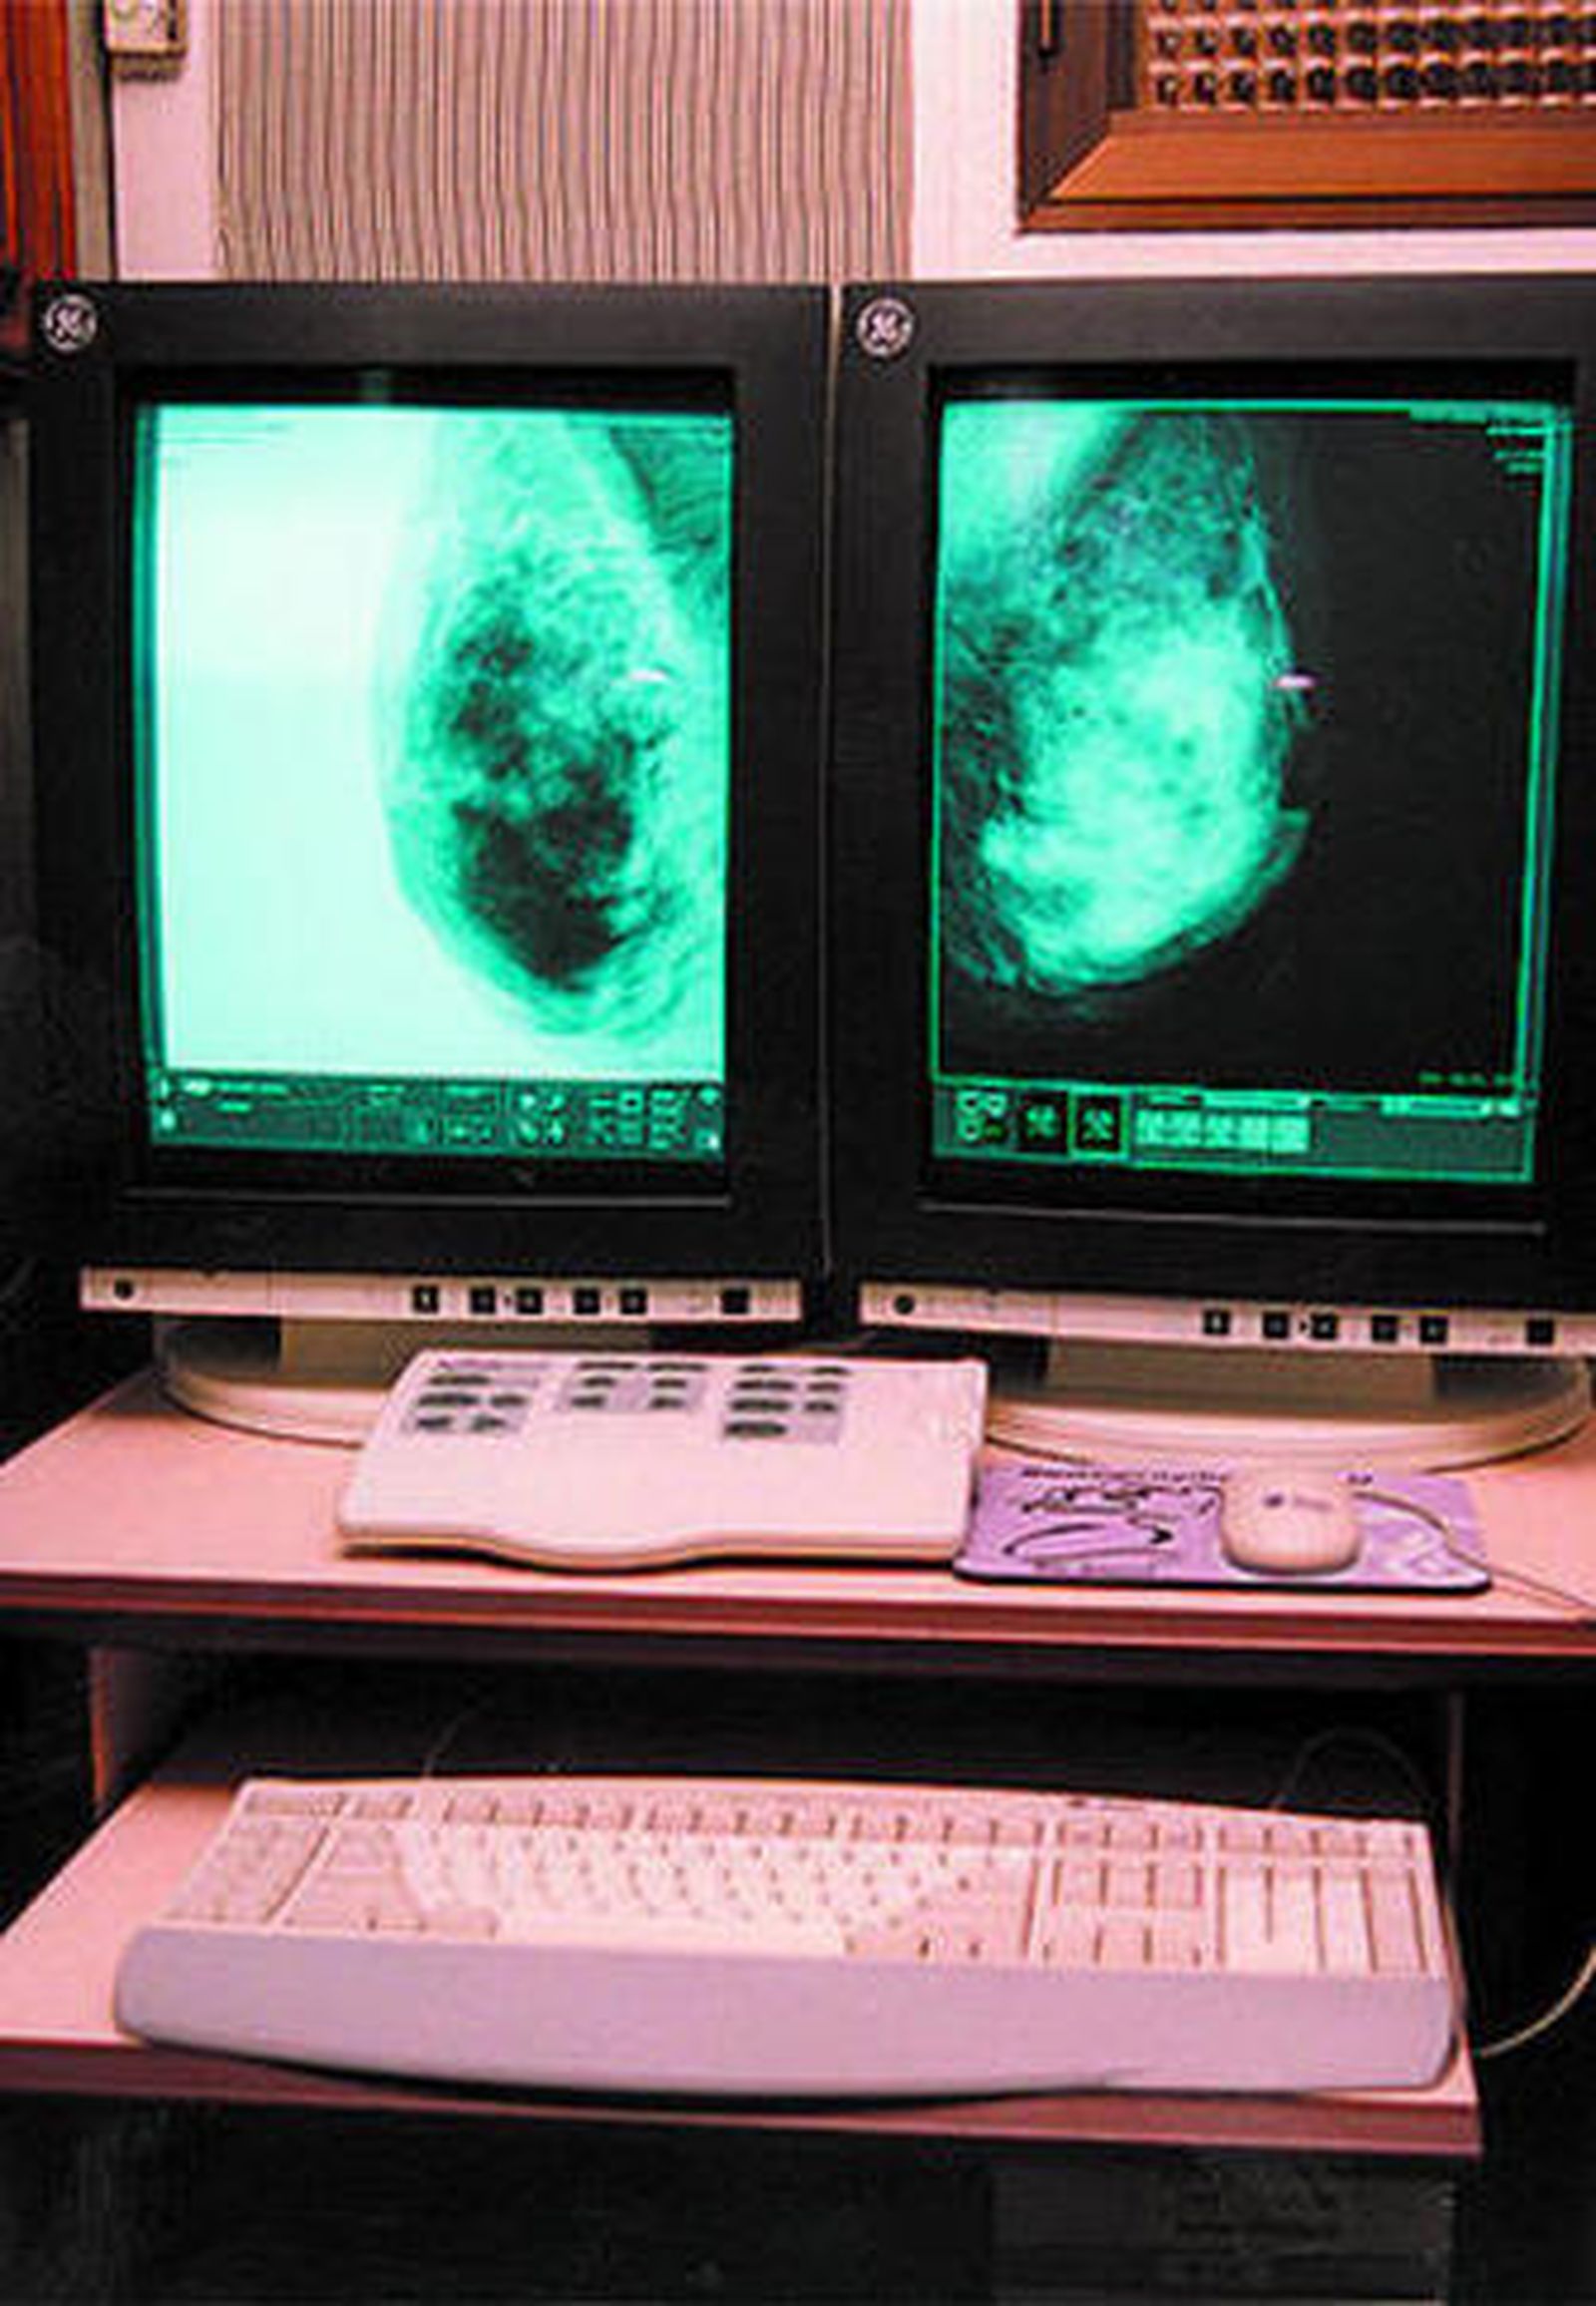

La metodología seguida es la realización de mamografías en Unidades de Exploración Específicas. Las mujeres que precisan ampliar el estudio diagnóstico o recibir tratamiento serán derivadas al hospital de referencia de la unidad.